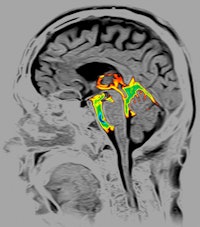

In MRI, Toshiba expects to receive 510(k) clearance from the U.S. Food and Drug Administration (FDA) later this year for Vantage Titan, the company's entry into the 3-tesla MRI segment. Toshiba is discussing a new M-Power user interface, which enables users to employ fewer mouse clicks when preparing sequences, such as its m-Vox isotropic brain imaging protocol.

| Image of cerebrospinal fluid in the brain acquired with Toshiba's Time-SLIP MRI protocol. |

Toshiba has also upgraded its 1.5-tesla Vantage Titan scanner with a new configuration known as Vantage Titan HSR. The enhancements include high slew rate gradients (gradient strength of 30 mT/m and slew rate of 203 mT/m/msec) and the M-Power user interface found on the 3-tesla model. Vantage Titan HSR is pending 510(k) clearance.